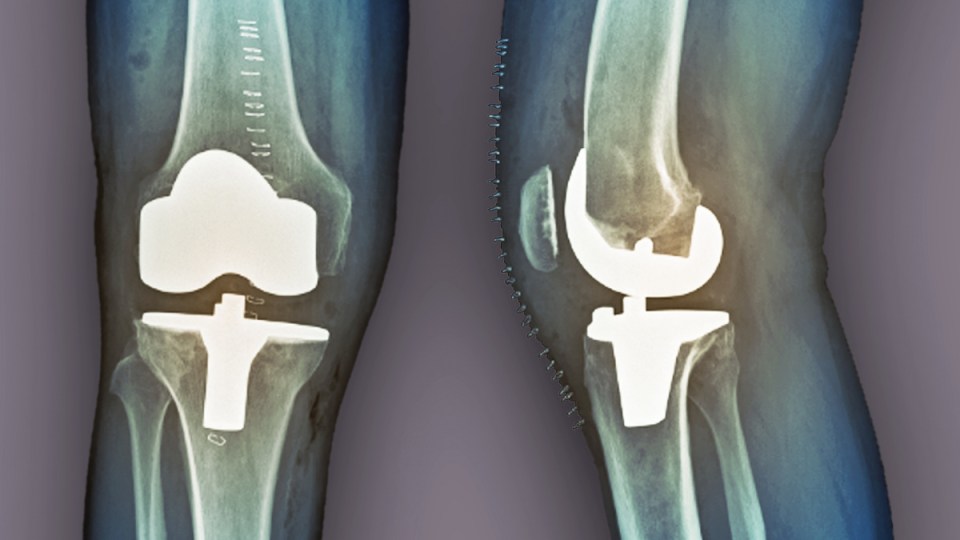

Hip and knee procedures are two of the most common and successful types of joint replacements worldwide.

Yet even in the best-case scenarios, infection, fracture, normal wear and tear or a reaction to wear particles may occur, the researchers said.

Often patients will require revision surgery, which can lead to increased fail rates, poorer function and greater cost than the initial surgery.